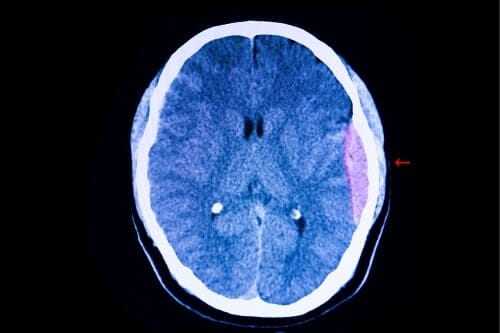

- гематомы внутри мозга, в височных областях, в подкорковых отделах;

В частности, невринома слухового нерва. Опухоль, даже в начальных стадиях заболевания, может приводить к изменениям на больной стороне. Меняются временные характеристики I-III пиков АСВП, снижается соотношение амплитуды V/I. В таких случаях показано МРТ или КТ исследование. Оно позволяет подтвердить или опровергнуть предположение о наличии невриномы.

При черепно-мозговой травме могут наблюдаться различные изменения амплитудно-временных характеристик АСВП.

Причиной патологических явлений служат нарушения кровообращения в области проводящих путей и ядер. Или их повреждение вследствие кровоизлияния, сдавления.

ЧМТ легкой степени не будет давать аномальных признаков со стороны АСВП. В результате средних и тяжелых ЧМТ, вызванные потенциалы могут регистрировать отклонения. Нарушения вызываются как первичным поражением ствола, так и вторичными причинами (сдавление отеком, гематомой).

Субарахноидальные кровоизлияния травматического и нетравматического генеза могут приводить к увеличению латентного времени II-V пиков и увеличению межпикового интервала I-III.